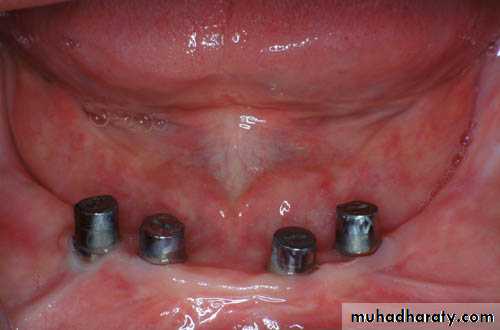

UNFAVORABLE ATTACHMENT APPLICATION:Stud Attachments

►Snap fasteners, mainly used for overdenture support, retention & stability.

► They consist of two main components:

Definition of stud attachments

Male projection

Female part► The two components interlock to form a retentive unit, mechanically attaching the superstructure to the abutments.

• ► Have applications for both root & implant supported prosthesis